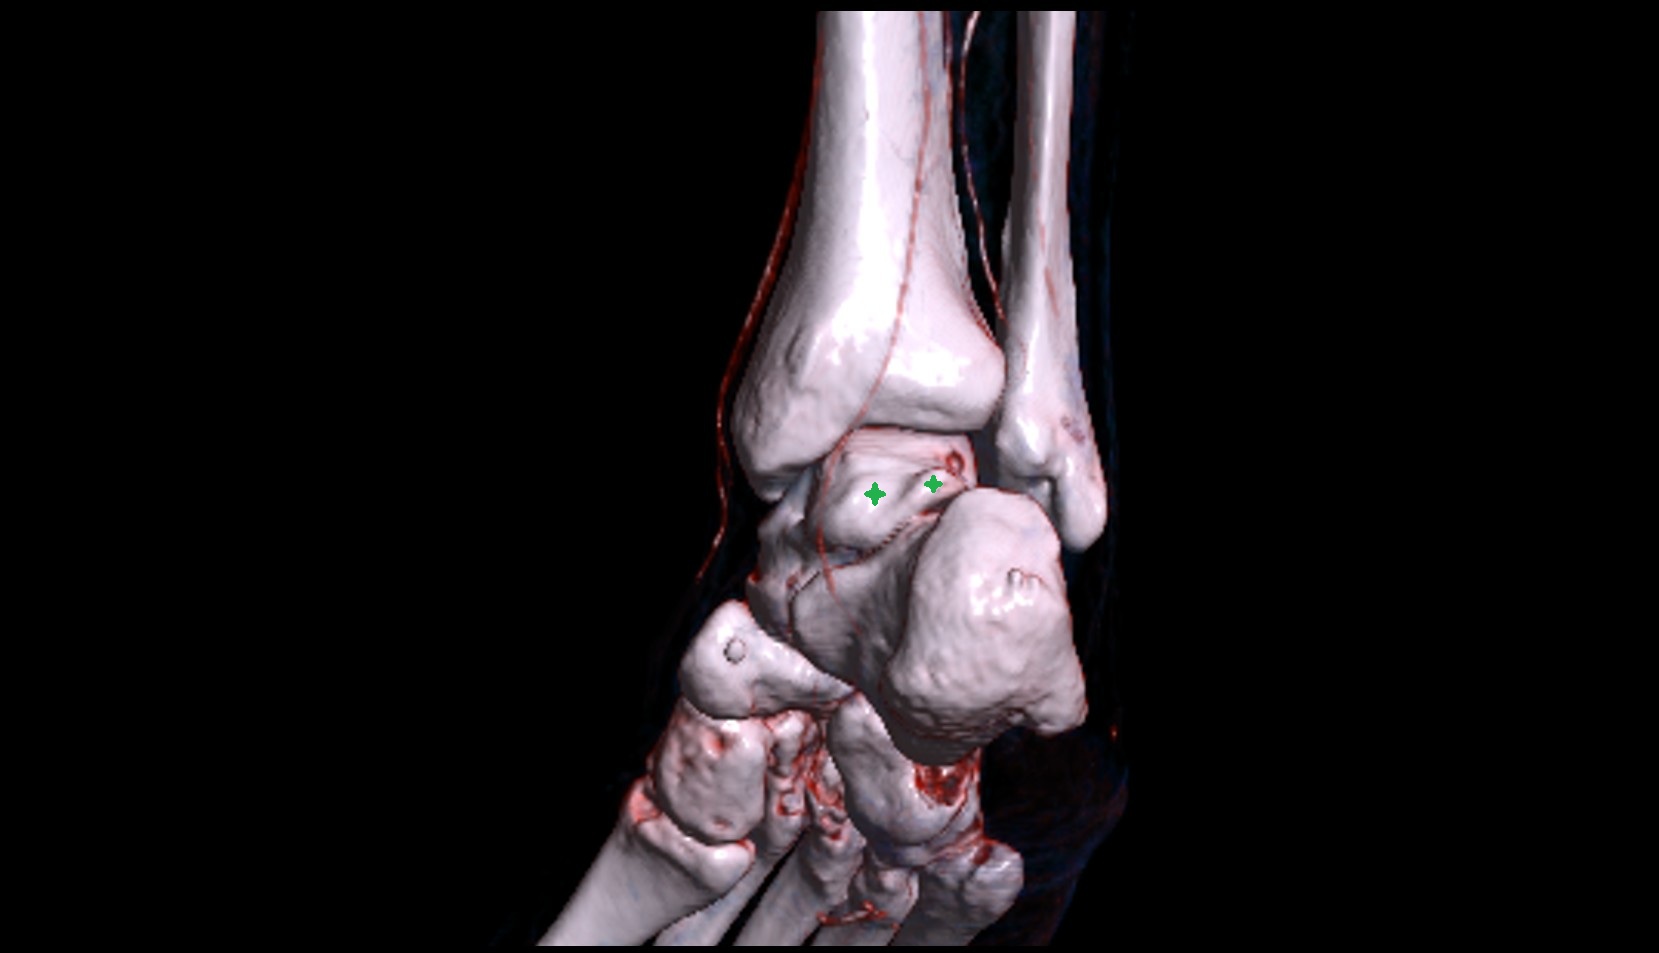

- Talus

- Head of talus

- Body of talus

- Neck of talus

- Posterior talar articular facet

- Calcaneus

- Anterior process of calcaneus

- Sustentaculum tali

- Ankle joint

- Talocalcaneal joint

- Talocalcaneonavicular joint